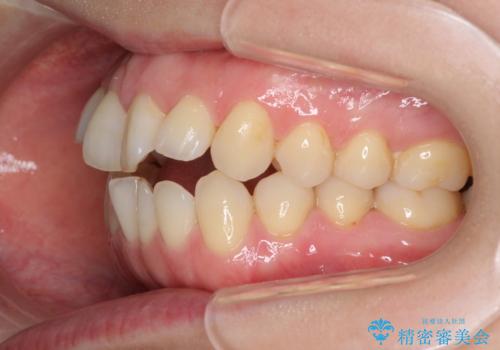

前歯の叢生とオープンバイト インビザラインでの矯正治療

- 前歯の開咬を気にして来院された患者様です。

開咬の治療は、前歯を閉じるように動かすとともに、上下臼歯を圧下(骨内にめり込ませる)させることで進めて行きます。

インビザラインは臼歯の圧下を効果的に行えるため、インビザラインを用いて矯正治療を行うこととしました。